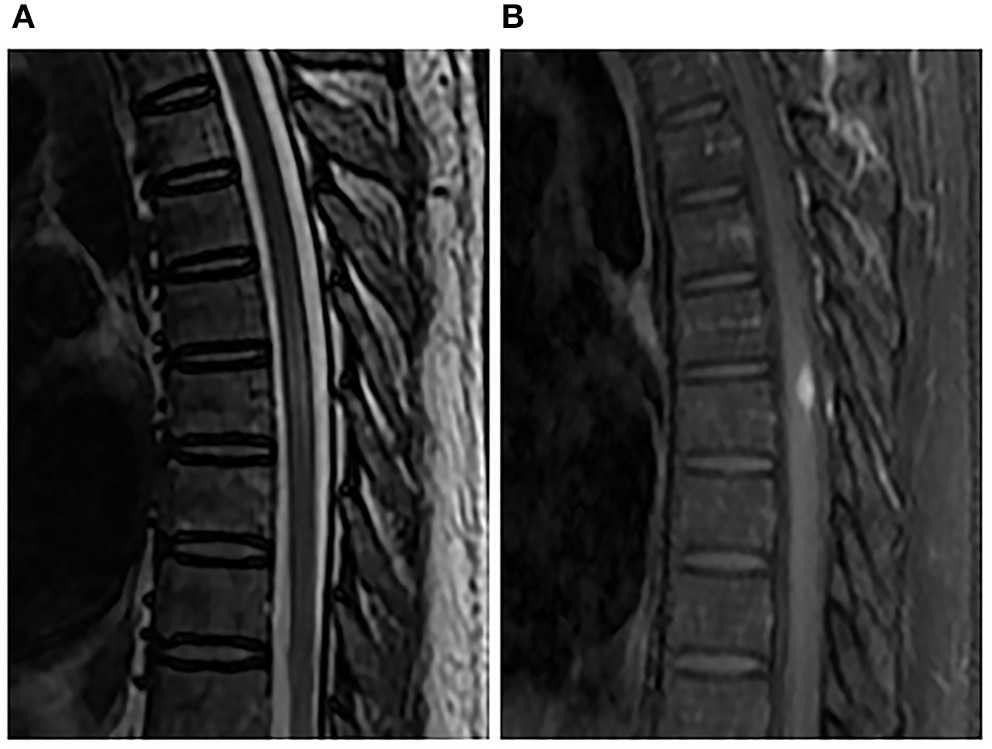

Figure 2

Spinal MRI performed 1 month after penicillin therapy. Sagittal T2-weighted image (A) and enhanced T1-weighted image (B) showed that the nodule and perilesional edema were reduced.